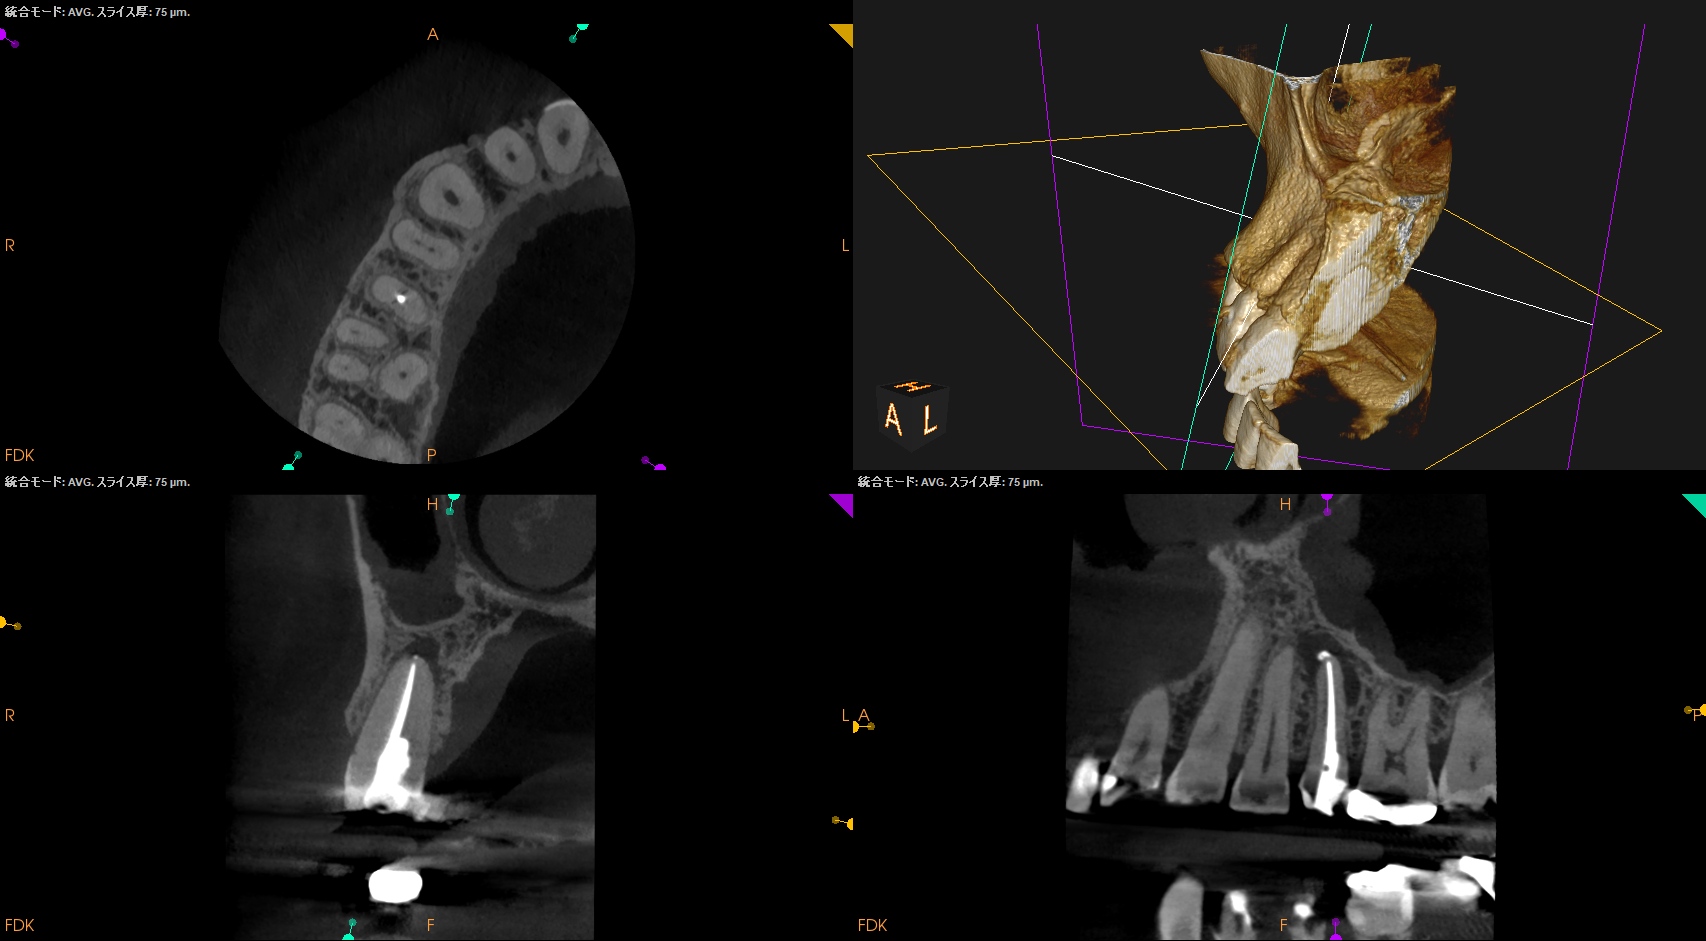

PA,CBCTを術後に撮影した。

問題はないだろう。